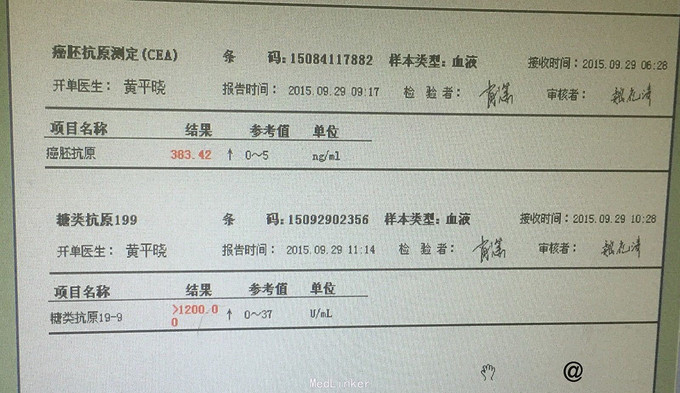

入院后完善相关检查 血常规:白细胞计数 13.84 ↑ 4~10 10^9/L。尿液分析及尿沉渣:白细胞 +- 阴性隐血 +- 阴性蛋白质 1+ 阴性糖 4+ 阴性,酮体 2+ 阴性。 生化全套2:白蛋白 32.9 ↓ 35~55 g/L球蛋白 39.9 ↑ 20~35 g/L白球比值 0.82 ↓ 1~2.5葡萄糖 20.85 ↑ 3.82~6.1 mmol。血脂肪酶及淀粉酶正常。红细胞沉降率 53 0~20 mm/h。糖化血红蛋白 11.7 ↑ <6 % 肿瘤全套2:癌胚抗原 405.13 ↑ 0~5 ng/ml,糖类抗原19-9 >1200.00 ↑ 0~37 U/mL。 头颅CT平扫未见明显异常。 胸部+上腹部CT提示:1.胃积气扩张,余上腹部CT平扫未见明显异常。2.肺气肿,支气管炎肺部表现;3.双肺间质性肺炎;4.主动脉硬化;5.主动脉窦致密影,考虑瓣膜钙化。 胰腺增强:1 胰腺CT增强未见明显异常。2 右肾小囊肿。 肠镜检查:大肠黑变病。胃镜检查:浅表性胃炎(2级)。 复查癌胚抗原 383.42 ↑ 0~5 ng/ml糖类抗原19-9 >1200.00 ↑ 0~37 U/mL,仍旧显著升高,为进一步排除肿瘤行病变,遂行盆腔磁共振检查:1.盆腔右侧占位,肿瘤性病变不除外,建议增强扫描。2.右侧附件区结节影,建议增强扫描。3.子宫肌层信号欠均匀,不除外腺肌病可能。4.盆腔少许积液。